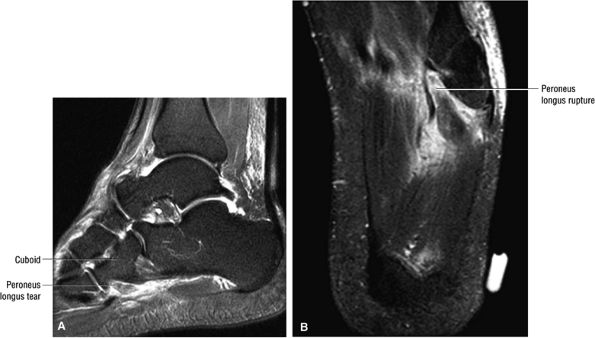

-

Distal thickening in the tibialis posterior tendinosis and tenosynovitis with or without partial to complete PTT tear

In asymptomatic patients, there is normal fat-suppressed marrow signal intensity on FS PD FSE images.